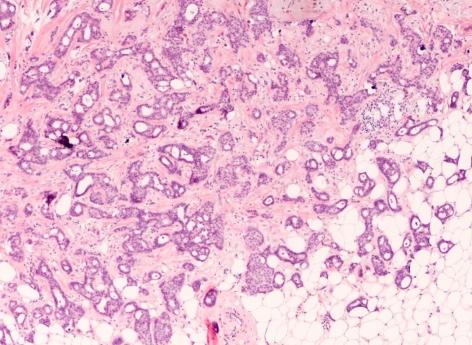

"Pour comprendre le risque de cancer du sein, vous devez d'abord comprendre les cellules mammaires normales, donc lorsque nous travaillons sur les thérapies préventives et même ciblées, nous essayons d’empêcher que les bons types de cellules se développent en cellules cancéreuses", explique Camila dos Santos, l’une des chercheuses. Pour cela, les scientifiques ont répertorié dans un catalogue toutes les cellules mammaires saines afin que, en cas de problème, les médecins puissent identifier son origine. Ils ont mené leurs travaux sur des tissus humains et de souris qui ont des profils génétiques similaires. Leurs travaux viennent d’être publiés dans la revue Journal of Mammary Gland Biology and Neoplasia.

Ce classement a été réalisé grâce à une technique connue sous le nom de séquençage d'ARN unicellulaire, qui permet d’analyser l’information génétique de chaque cellule. Ainsi, les scientifiques ont étudié l'activité de plusieurs gènes contenus dans plus de 15 000 cellules humaines et animales. "Nous avons vraiment créé tout un catalogue de nombreux gènes pour chaque population cellulaire afin de mieux les définir, développe Samantha Henry, ayant participé à l’étude. Et quand je dis qu'il y avait beaucoup de gènes, il y avait beaucoup de gènes et il a fallu y passer énormément de temps.” L’un des groupes de cellules comprenait celles réceptives aux oestrogènes - un type d’hormones féminines - qui peuvent être ciblées lors des traitements de certains cancers du sein. Mais, dans ce groupe, les chercheurs ont identifié des sous-populations de cellules, en fonction de leurs réponses aux thérapies. Référencer les différentes caractéristiques et réactions des cellules n’avait jamais été fait auparavant.